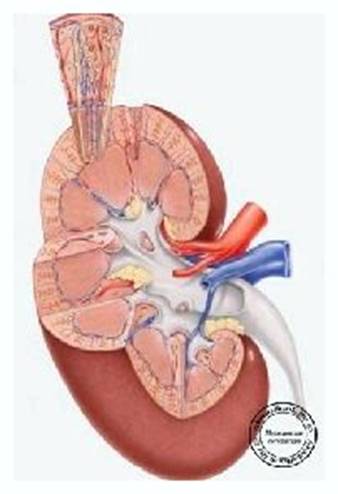

Нирка

складається

з коркового і

мозкового

шарів. У

корковому

шарі

містяться

клубочки

(гломерули) –

капілярні

петлі

ниркової

артерії.

Кожний клубочок,

охоплений

спеціальною

капсулою Шумлянського–Боумена,

утворює

мальпігійове

тільце. До

кожного

клубочка

підходить привідна

артеріола (vas

аfferens); її петлі і

утворюють

клубочок;

відводить

кров з

клубочка відвідна

еfferens). Від

капсули

відходить

шийка

канальця.

Більшість

канальців розміщена

в мозковому

шарі.

Структурною

одиницею

нирки є

нефрон, який

з мальпігійового

тільця і

системи

ниркових

канальців. У

нирках є

близько 2 млн.

клубочків, а

площа

фільтруючої

поверхні

епітелію

канальців

становить 50 м2.